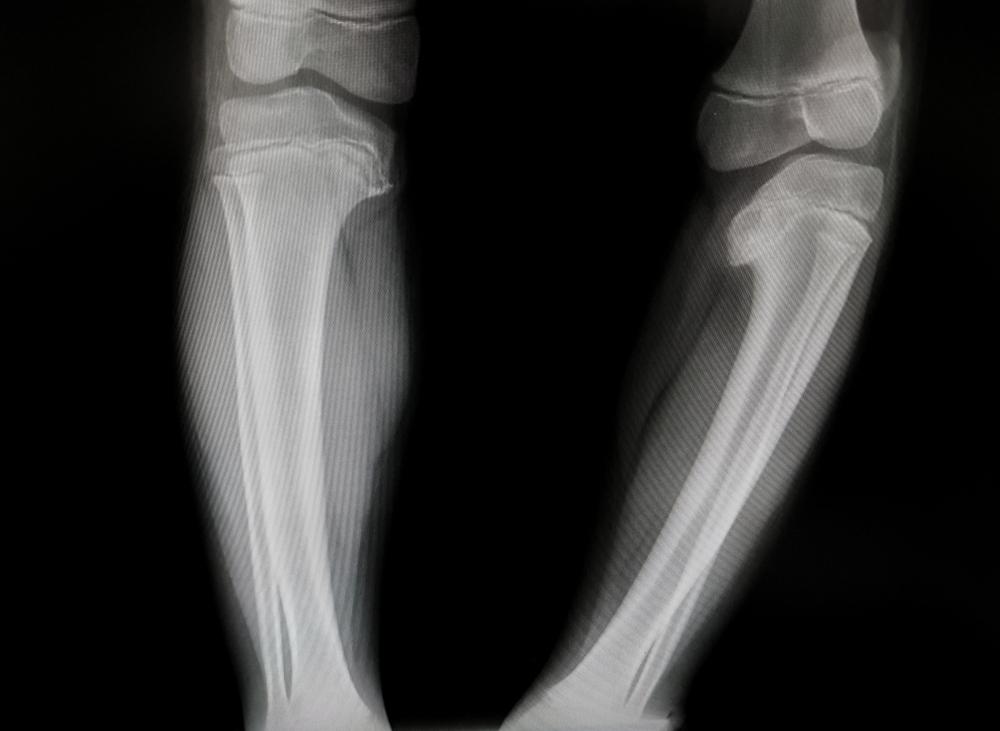

Penyakit Blount atau tibia vara adalah suatu kondisi pada tulang anak yang memengaruhi lempengan pertumbuhan di sekitar lutut.

Akibatnya, salah satu atau kedua tulang kaki anak di bagian bawah lutut tidak dapat tumbuh lurus, melainkan akan terlihat bengkok dan menyerupai huruf C.

Namun, perubahan struktur tulang (deformitas) hanya terjadi pada tulang kering (tibia) yang terletak di depan betis.

Sementaa itu, perubahan struktur tulang (deformitas) terjadi pada tulang paha (femur) dan tibia.

Untuk memastikan kondisi yang dialami, dokter juga akan menjalankan pemindaian dengan foto Rontgen.

Pemindaian ini bertujuan untuk membantu dokter melihat pertumbuhan tulang anak dan mendeteksi penyebab kebengkokan pada tulang.